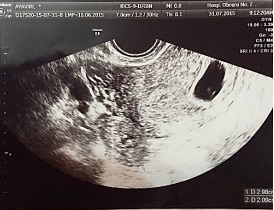

El ultrasonido transvaginal reveló útero en AVF de forma y contornos normales, dimensiones aumentadas de tamaño a expensas de saco gestacional ortotópico con embrión único vivo de 7 mm de LCC con actividad cardiaca ( Figura 1), correspondiente a seis semanas de gestación, una formación anexial ovoide de 31x19 mm en anexo derecho; Douglas con líquido libre escaso.

Se concluyó que se trataba de un embarazo heterotopico: uno intrauterino de 6,4 semanas con vitalidad corroborada y otro ectópico tubario derecho ( Figura 2).